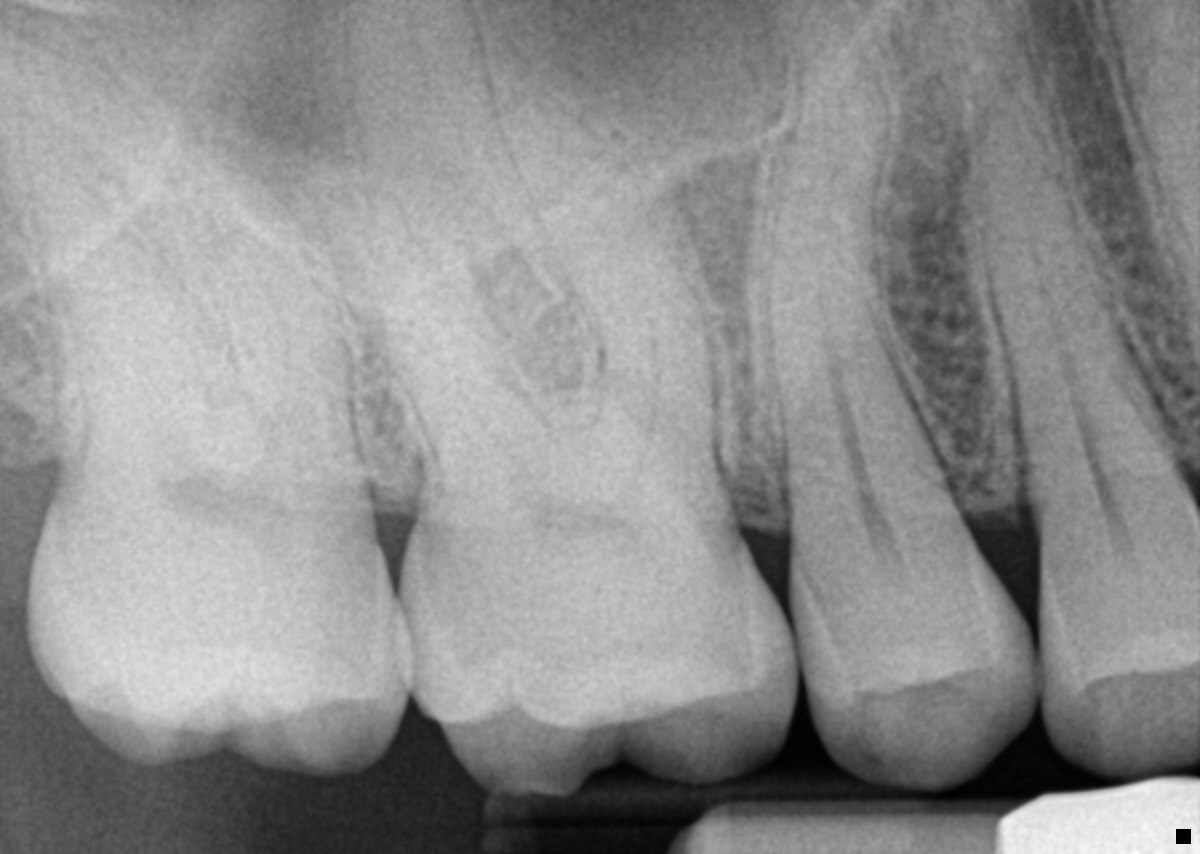

FMX 7-17-1416